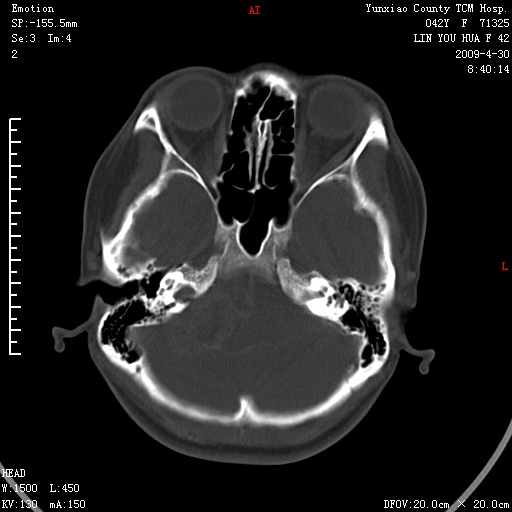

右侧桥小脑角区肿瘤,高密度囊变有显著强化,骨窗见内听道显著扩大,考虑听神经瘤可能性大

内听道扩大,支持考虑听神经瘤可能性大。